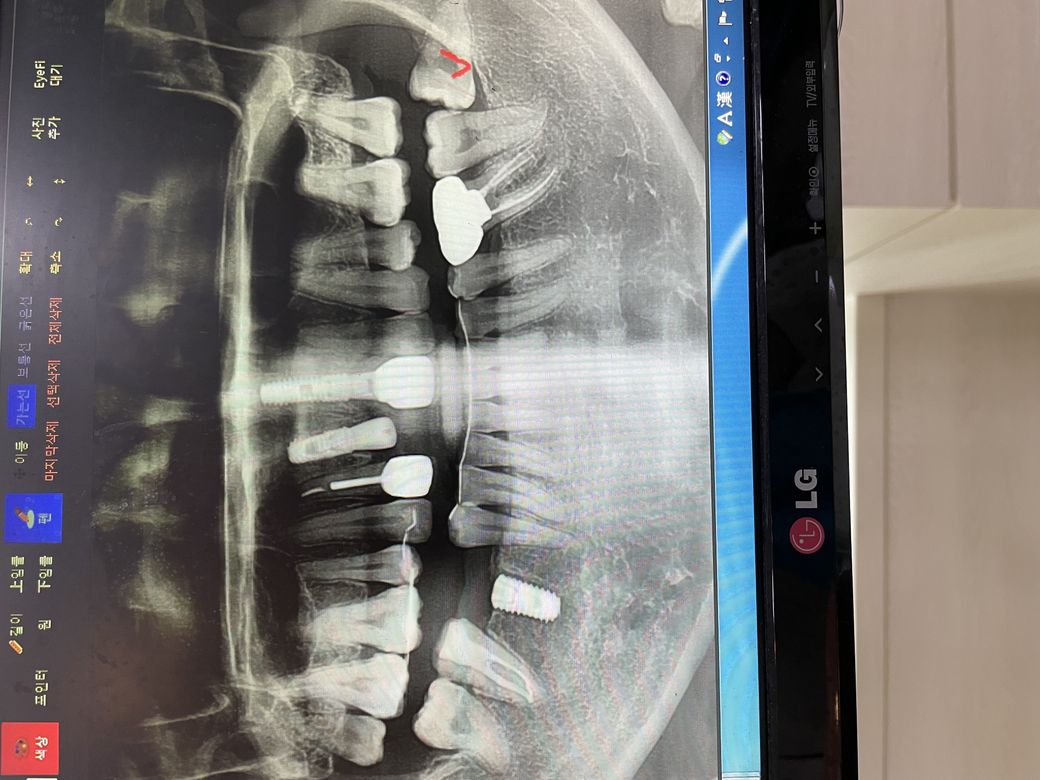

상악 앞니와 우측 아래 어금니2군데 도요ㅣ에 임플란트 픽쳐스 식립 후 오늘 일주일째

엑스레이 상으로는 식립이 잘 된간가요?ㅠㅠ

임플란트는 엑스레이상 문제없어보입니다.

확답을 드리긴 힘들지만 임플란트에는 큰 이상이 없어 보이긴 합니다.

해당 사진으로는 실밥이 보이지 않습니다. 실밥이 잔류되어 있는 것은 회복에 좋지 않습니다. 따라서 실밥이 맞다면 다시 치과를 내원하여 실밥을 제거하는 것이 필요합니다. 엑스레이 상에서 임플란트 픽스쳐 식립은 잘되어 있습니다. 따라서 실밥 잔류되어 있는 것만 제거하시면 될 것 같습니다.

엑스레이상으로 식립이 잘 되어있습니다.

방사선사진에서 임플란트 식립은 잘된것 같습니다.